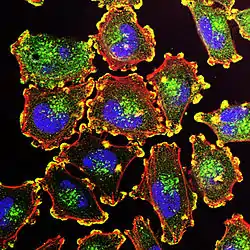

Melanoma, also redundantly known as malignant melanoma,[7][8][9] is a type of cancer that develops from the pigment-producing cells known as melanocytes.[1] Melanomas typically occur in the skin, but may rarely occur in the mouth, intestines, or eye (uveal melanoma).[1][2] In women, they most commonly occur on the legs, while in men, they most commonly occur on the back.[2] About 25% of melanomas develop from moles.[2] Changes in a mole that can indicate melanoma include an increase in size, irregular edges, change in color, itchiness, or skin breakdown.[1]

Pathophysiology

The earliest stage of melanoma starts when melanocytes begin out-of-control growth. Melanocytes are found between the outer layer of the skin (the epidermis) and the next layer (the dermis). This early stage of the disease is called the radial growth phase, when the tumor is less than 1 mm thick, and spreads at the level of the basal epidermis.[41] Because the cancer cells have not yet reached the blood vessels deeper in the skin, it is very unlikely that this early-stage melanoma will spread to other parts of the body. If the melanoma is detected at this stage, then it can usually be completely removed with surgery.

The host elicits an immunological reaction against the tumor during the VGP,[43] which is judged by the presence and activity of the tumor infiltrating lymphocytes (TILs). These cells sometimes completely destroy the primary tumor; this is called regression, which is the latest stage of development. In certain cases, the primary tumor is completely destroyed and only the metastatic tumor is discovered. About 40% of human melanomas contain activating mutations affecting the structure of the B-Raf protein, resulting in constitutive signaling through the Raf to MAP kinase pathway.[44]

The entire genomes of 25 melanomas were sequenced.[48] On average, about 80,000 mutated bases (mostly C>T transitions) and about 100 structural rearrangements were found per melanoma genome. This is much higher than the roughly 70 mutations across generations (parent to child).[49][50] Among the 25 melanomas, about 6,000 protein-coding genes had missense, nonsense, or splice site mutations. The transcriptomes of over 100 melanomas has also been sequenced and analyzed. Almost 70% of all human protein-coding genes are expressed in melanoma. Most of these genes are also expressed in other normal and cancer tissues, with some 200 genes showing a more specific expression pattern in melanoma compared to other forms of cancer. Examples of melanoma specific genes are tyrosinase, MLANA, and PMEL.[51][52]

UV radiation causes damage to the DNA of cells, typically thymine dimerization, which when unrepaired can create mutations in the cell's genes. This strong mutagenic factor makes cutaneous melanoma the tumor type with the highest number of mutations.[53] When the cell divides, these mutations are propagated to new generations of cells. If the mutations occur in protooncogenes or tumor suppressor genes, the rate of mitosis in the mutation-bearing cells can become uncontrolled, leading to the formation of a tumor. Data from patients suggest that aberrant levels of activating transcription factor in the nucleus of melanoma cells are associated with increased metastatic activity of melanoma cells;[54][55][56] studies from mice on skin cancer tend to confirm a role for activating transcription factor-2 in cancer progression.[57][58]